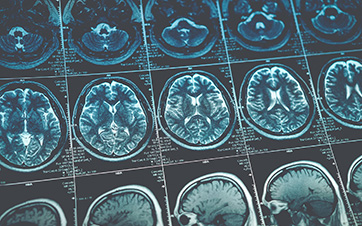

MRI for brain tumor detection provides detailed images of the brain. This allows doctors to locate tumors and assess their size and shape precisely.

Detailed images are crucial for treatment planning. It helps determine the most appropriate surgical approach. Not only that, but it provides accurate targeting of radiation therapy.

MRI also gives insight into the impact of the tumor on surrounding tissues. As a result, the technology enables doctors to assess potential complications and plan interventions accordingly.

The resulting images provide healthcare professionals with valuable information about the location and characteristics of brain tumors. This allows for accurate diagnosis, treatment planning, and monitoring of tumor progression over time.